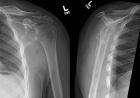

22 year old male c/o left shoulder pain while doing push-ups

Zoom image: Radiological image Radiological image.